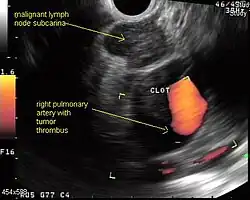

Endoscopic ultrasound (EUS) is an endoscopic technique where a miniaturized ultrasound probe is passed through the mouth into the upper gastrointestinal tract to investigate organs and structures close to the esophagus, stomach, or duodenum, such as the lung. In 1993, Wiersema published the first description of EUS to diagnose and stage lung cancer,[31] done by advancing a fine needle through the esophagus into adjacent lymph nodes. Numerous subsequent studies have shown this general methodology to be effective, very safe, minimally invasive, and very well tolerated. Given these advantages, many authorities think that EUS together with endobronchial ultrasound (EBUS) enhances lung cancer diagnosis and staging.[32]

Endoscopic ultrasound (EUS)

A metaanalysis published in 2007, based on 1,201 cancers in 18 high-quality clinical trials carefully selected by predefined criteria from the literature, systematically examined the performance of EUS-guided FNA in NSCLC staging. Two scenarios were considered: the setting of enlarged lymph nodes on CT (suggestive but not diagnostic of cancer), and the obverse scenario of an absence of lymph node enlargement on CT (suggestive but not diagnostic of no cancer).[28] Overall, in both settings, minor complications were reported in 0.8% of procedures; no major complications were recorded. EUS-FNA in enlarged discrete mediastinal lymph nodes had an excellent pooled sensitivity (8 studies) of 90% (95% CI, 84 to 94%) and specificity of 97% (95% CI, 95 to 98%). EUS-FNA in the setting of no enlarged mediastinal lymph nodes on CT had a pooled sensitivity (4 studies) of 58% (95% CI, 39 to 75%) and specificity of 98% (95% CI, 96 to 99%). Although this sensitivity (58% in CT-negative disease) might on first consideration seem disappointing, if EUS is performed as a staging test it can help avoid more invasive staging procedures, or surgery, if positive (for the presence of cancer). In other words, an EUS that has a positive result (shows cancer) will avoid further needless surgery, whereas a result not showing cancer may be false-negative, and probably requires an excisional biopsy technique for confirmation, such as VATS or mediastinoscopy.